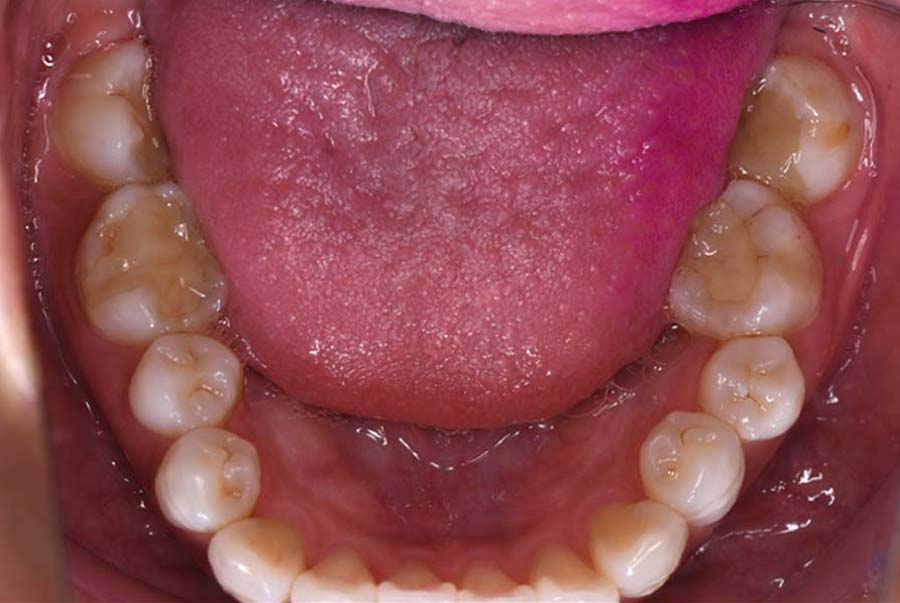

| 治療内容 | ①スプリントを装着 ②副子を装着 ③2024年4月 口腔内反映開始 ④副子を入れた状態の所まで咬合を挙上 (バイトアップ) ⑤2024年5月 上顎前歯部8本へ仮歯(TEK) を装着 |

2024年 10月 下顎MTM開始

バイトアップ後